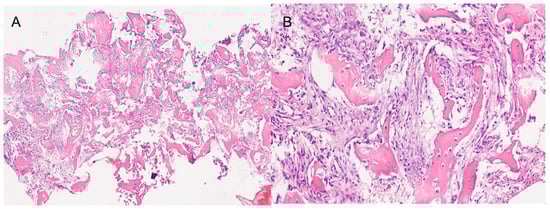

Both histological reports confirmed the diagnosis of fibrous dysplasia, showing a bone-fibrous fragment including bone trabeculae with irregular distribution with a crossed fibers structure with marked remodeling, and a non-atypic fibrous tissue with several vascular structures with thick and mineralized walls (Figure 3).

Moreover, in continuity with this tissue, they showed a de-epithelialized mucosa with normal gland structures. The Ki67 expression shown was <5%.

Figure 3. The histopathological images show a section of the middle turbinate. (A) 4× magnification. (B) 20× magnification. Both images show the main characteristics of fibrous dysplasia, such as fibrous tissue intermixed with irregularly distributed bony trabeculae.